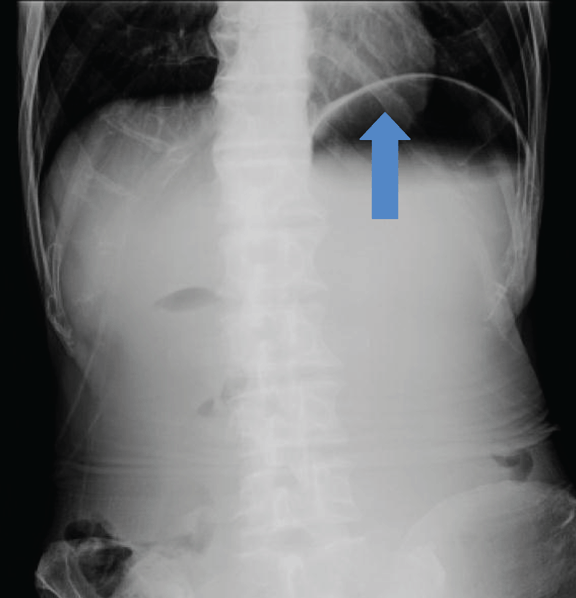

A 64-year-old schizophrenic elderly male was admitted in Singapore government hospital for epigastric pain of 1 day duration associated with a two-day history of vomiting. The character of the vomitus was uncertain. He had lost 30–40 kg of weight over several months. The patient denied postprandial pain and had no previous similar episode. He had no past history of surgery and was not on any psychiatric medication. The patient had paranoid schizophrenia but was never compliant with medications. He lived alone and had persecutory thoughts. He was suspicious of people around him and barred all windows and rooms. He also mentioned cameras watching him and “people” want to harm him. He refused to go out and consumed mainly instant noodles for several years. One month before this admission, he was admitted for hypoglycemia secondary to poor oral intake and incidentally had low calcium and vitamin D deficiency. His vital signs were stable on admission. He appeared comfortable but was severely cachectic with a body mass index of 10.9 kg/m2 (weight 34.4 kg, height 178 cm). The abdomen was scaphoid, distended and tender over epigastric area with no sign of peritoneal irritation and succussion splash was positive. Per rectal examination was unremarkable. Initial laboratory studies were largely unremarkable besides the elevated total white, low creatinine and urea. Supine and erect plain abdominal radiograph showed a grossly distended stomach and collapsed bowel distally. (Figure 1) In view of the distended abdomen, positive succession splash and dilated stomach on abdominal radiograph, our initial impression was gastric outlet obstruction. Patient was kept nil by mouth and nasogastric tube was inserted to maintain gastric and duodenal decompression. Nasogastric tube immediately aspirated 2.2 liters of bilious fluid. Upper gastrointestinal series showed distended stomach and duodenum to the level of mid third part, where an abrupt cut-off occurred. (Figure 2) To determine the aetiology, contrast-enhanced computed tomography (CT) scan of the abdomen was arranged and the third portion of the duodenum was clearly ‘pinched’ by the abdominal aorta and the superior mesenteric artery. The aorta-SMA angle was 4 degrees and the aortomesenteric distance measured 5.6 mm. (Figure 3) (Figure 4) In addition, CT scan also revealed obvious reduction of the intra-abdominal fat. There was no free intraperitoneal air. Based on the history, examination and imaging findings, we diagnosed SMA syndrome. Endoscopic guided insertion of nasojejunal tube was performed for enteral feeding as patient was unable to tolerate any oral intake due to duodenal obstruction. (Figure 5) However, the patient was not cooperative with nasojejunal tube feeding. Subsequently, he developed hypoglycemia, hypokalemia and hypotension that was refractory to resuscitation. Consciousness deteriorated and the patient passed away. | ||||||